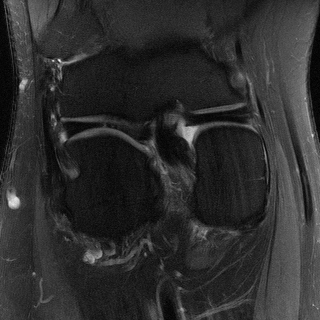

Edge preserving has always been a crucial concern in the design of reconstruction models. To improve the quality of reconstructed images and preserve image edges, some works suggested introducing edge priors in the original restoration problem to preserve image edges [4, 34]. However, they will suffer from complicated algorithm design and time-consuming training processes. Recently, some more efficient methods have been proposed to use edge maps as external guidance for image restoration. For example, Yang et al. [48] used off-the-shelf edge detectors to extract image edges from the degraded images. Fang et al. [12] predicted image edges by constructing an edge reconstruction network. Huang et al. [18] designed a novel dual discriminator GAN framework for solving fast multi-channel MRI, in which one GAN network is built for edge information enhancement. Inspired by these methods, we also consider introducing image edge prior as external guidance to MRI reconstruction since 1) image edges are prominent and distinguishable features in MRI (see Fig. 1), which can serve as a good guide to the model to recover high-frequency details; 2) the ground truth edges can be easily fetched via ordinary edge extraction operators, like Canny, Sobel, and Prewitt, which means that the edge maps can be learned in a data-driven manner. However, how to effectively utilize image edge priors to guide image reconstruction still remains a challenge. In some methods, edge information was simply concatenated with the input image and passed to the next stages. Though this is a simple way to utilize the edge priors, it may not give full play to the guiding role of the edge priors. Therefore, in this work, we want to explore a more efficient and effective mechanism to fully take advantage of image edge priors.

(a)

(b)

(c)

fastMRI is a large-scale MR dataset jointly established by Facebook AI Research and NYU Langone Health. It provides both knee and brain datasets for evaluation. In our work, we use the multi-coil knee dataset, which was acquired on three clinical 3T systems or one clinical 1.5T system using a 15-channel knee coil array. The dataset includes data from two pulse sequences, yielding coronal proton-density weighting with (PDFS) and without (PD) fat suppression. As is shown in Fig. 1, PD images usually contain more structural and prominent edge features than PDFS images, which suggests that it is more challenging to use edge guidance on PDFS datasets. Therefore, we explore the effectiveness of EAMRI on these two modalities. Following [13], for both PD and PDFS knee datasets, we separately filter out 227 volumes (8332 slices) for training and 24 volumes (1665 slices) for testing. The dataset is centrally cropped to .